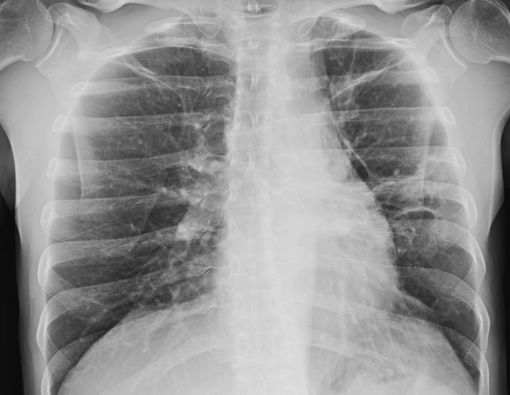

Kalsifikasi menyebabkan keberadaan granuloma lebih mudah terlihat pada tes pencitraan seperti rontgen dada atau CT scan.

Beberapa granuloma paru yang dideteksi melalui rontgen dada dapat terlihat seperti tumor penyebab kanker. Tetapi perlu dicatat, granuloma bukanlah kanker. Nodul ini bahkan seringkali tidak menimbulkan gejala apa pun.